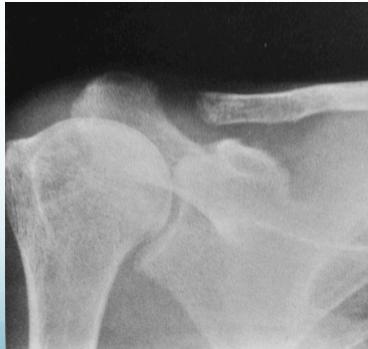

- Lateral end of clavicle resorption

- Lateral end of clavicle